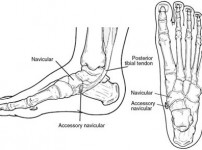

부주상골 통증 원인과 부주상골증후군 진단이 필요한 이유

1. 발 안쪽에 하나 더 있는 뼈, '부주상골증후군'이란 무엇인가? 안녕하세요. 발의 편안함을 위해 정성을 다하는 정형외과 전문의이자, 강동구 서울건우정형외과 대표원장 최…